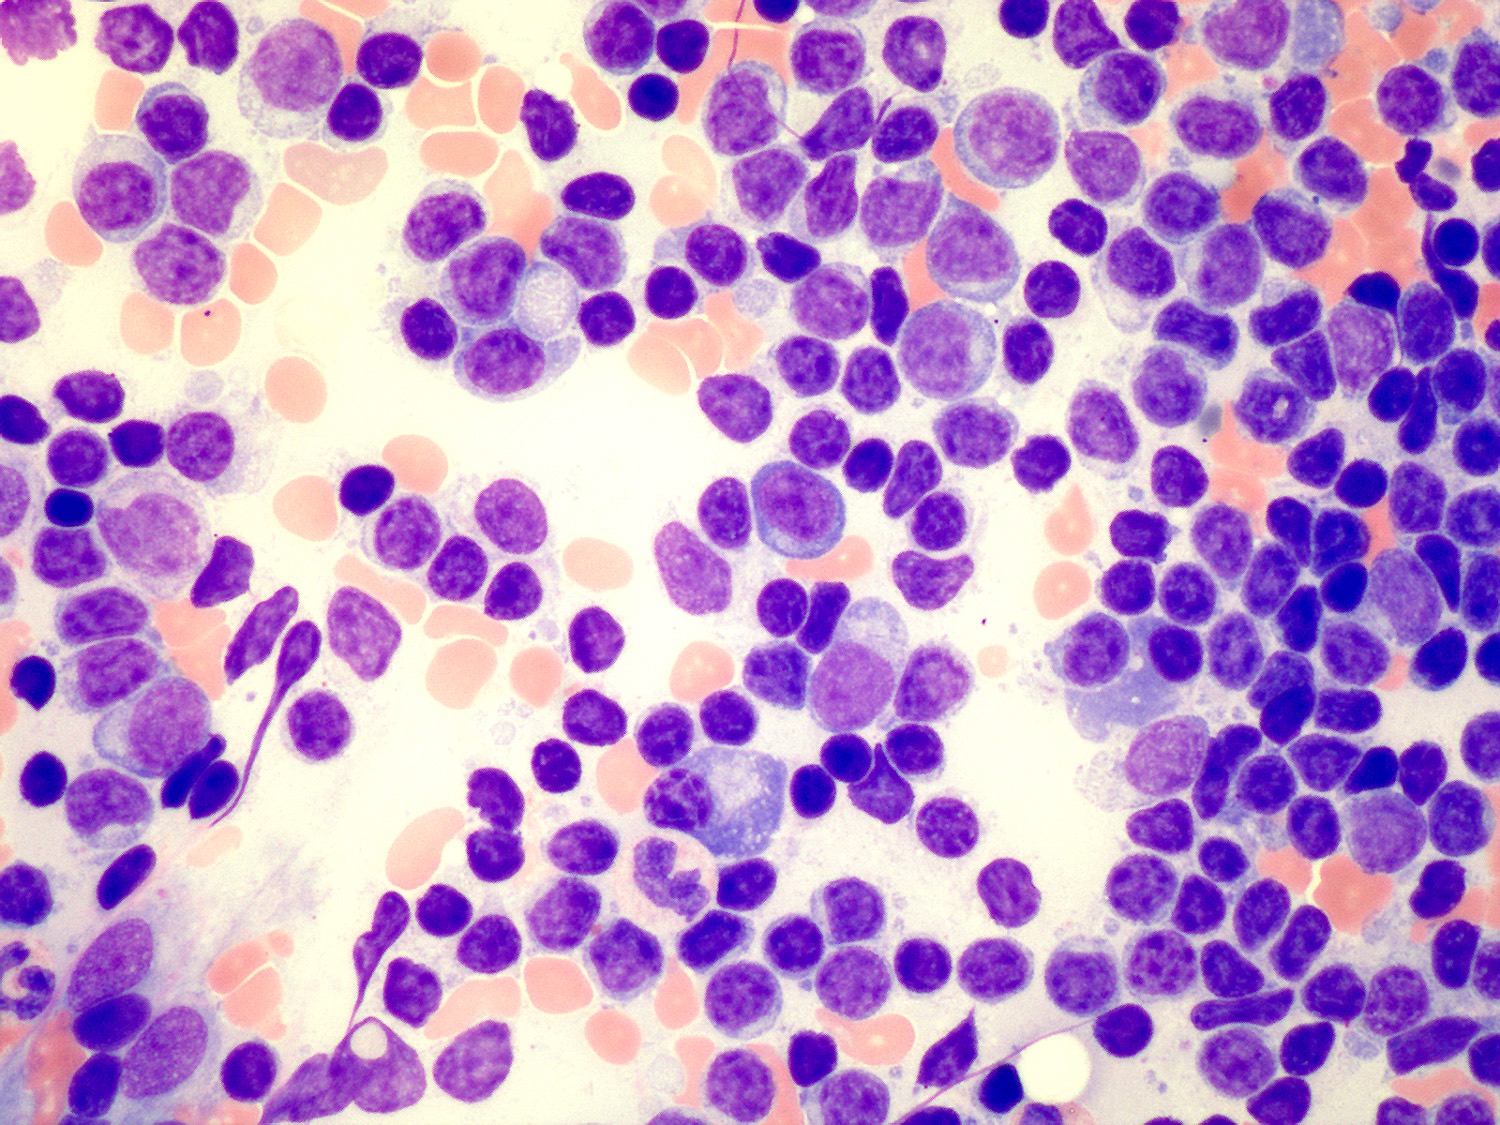

Microscopic (histologic) description

- Blood

- Often shows lymphocytosis with a spectrum of lymphocytes, plasmacytoid lymphocytes and plasma cells

- Rouleaux formation of red blood cells is routinely seen

- Cold agglutinin or cryoglobulin may be present

- Bone marrow (Arch Pathol Lab Med 2013;137:580)

- Involvement in almost all cases

- Aspirate is the most helpful sample in morphologic diagnosis

- Predominantly small lymphocytes with a variable number of plasmacytoid lymphocytes and plasma cells

- Mast cells are typically increased; most prominent within particles on aspirate smears

Microscopic (histologic) images

Contributed by Ling Zhang, M.D.

- Aspirate smear: The Wright stained bone marrow aspirate smears are cellular, with adequate spicules included for evaluation. Megakaryocytes are decreased in number, when identified, showing normal morphology. Myeloid and erythroid precursors show progressive maturation but are relatively decreased in number. The estimated M:E ratio is 4:1. The cellularity is composed of mostly atypical lymphocytes (84% of differential count). These atypical lymphocytes are predominantly small in size, with oval or slightly irregular nuclear contours, mature chromatin and small amount of basophilic cytoplasm. Rare atypical lymphocytes are medium in size, with plasmacytoid differentiation. Plasma cells account for 4.8% of the differential count. Scattered mature mast cells are present in the background.